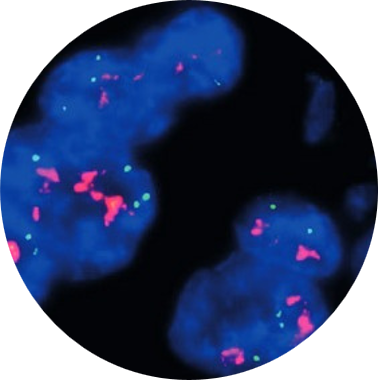

Hibridização

In Situ

Técnica que utiliza a especificidade de sondas de DNA sintetizadas com sequencias complementares específicas para pesquisa de segmentos gênicos de agentes etiológicos, geralmente virais.

O sinal positivo é possível se conseguir adicionando moléculas cromogênicas às sondas e revelando-as à semelhança das reações imuno-histoquímicas, porém com maior sensibilidade e especificidade.

As principais aplicações são: